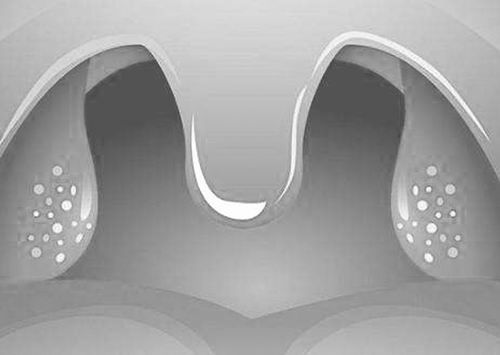

扁桃体反复发炎,切还是留?专家认为,应理性对待,科学选择。图片来源:care.qm120.com

扁桃体反复发炎,切还是留?关于儿童扁桃体的切除,我国以及英、美等国都有详细、明确的临床实践指南,其中包括特殊情况患者的评估、干预和围手术期的管理等。

路武豪表示:“国内的扁桃体切除,更多是因为以打鼾为主诉的睡眠呼吸障碍。这些病情会导致孩子生长缓慢、智力发育落后、遗尿症,患心血管疾病的可能性也会因此增加。”同时,扁桃体肥大、腺样体肥大往往相伴相生,如果坐视不理还可能形成腺样体面容,孩子颜值受损也是让家长焦虑的事儿。

扁桃体是咽淋巴环的一部分,3岁前对人体免疫系统的建立有很大帮助,3岁后可由其他免疫器官完全替代。路武豪表示,他迄今尚未碰到过扁桃体切除术后免疫力下降的案例,即便有些免疫系统指标会在术后短期内发生改变,人体也会迅速适应调整。